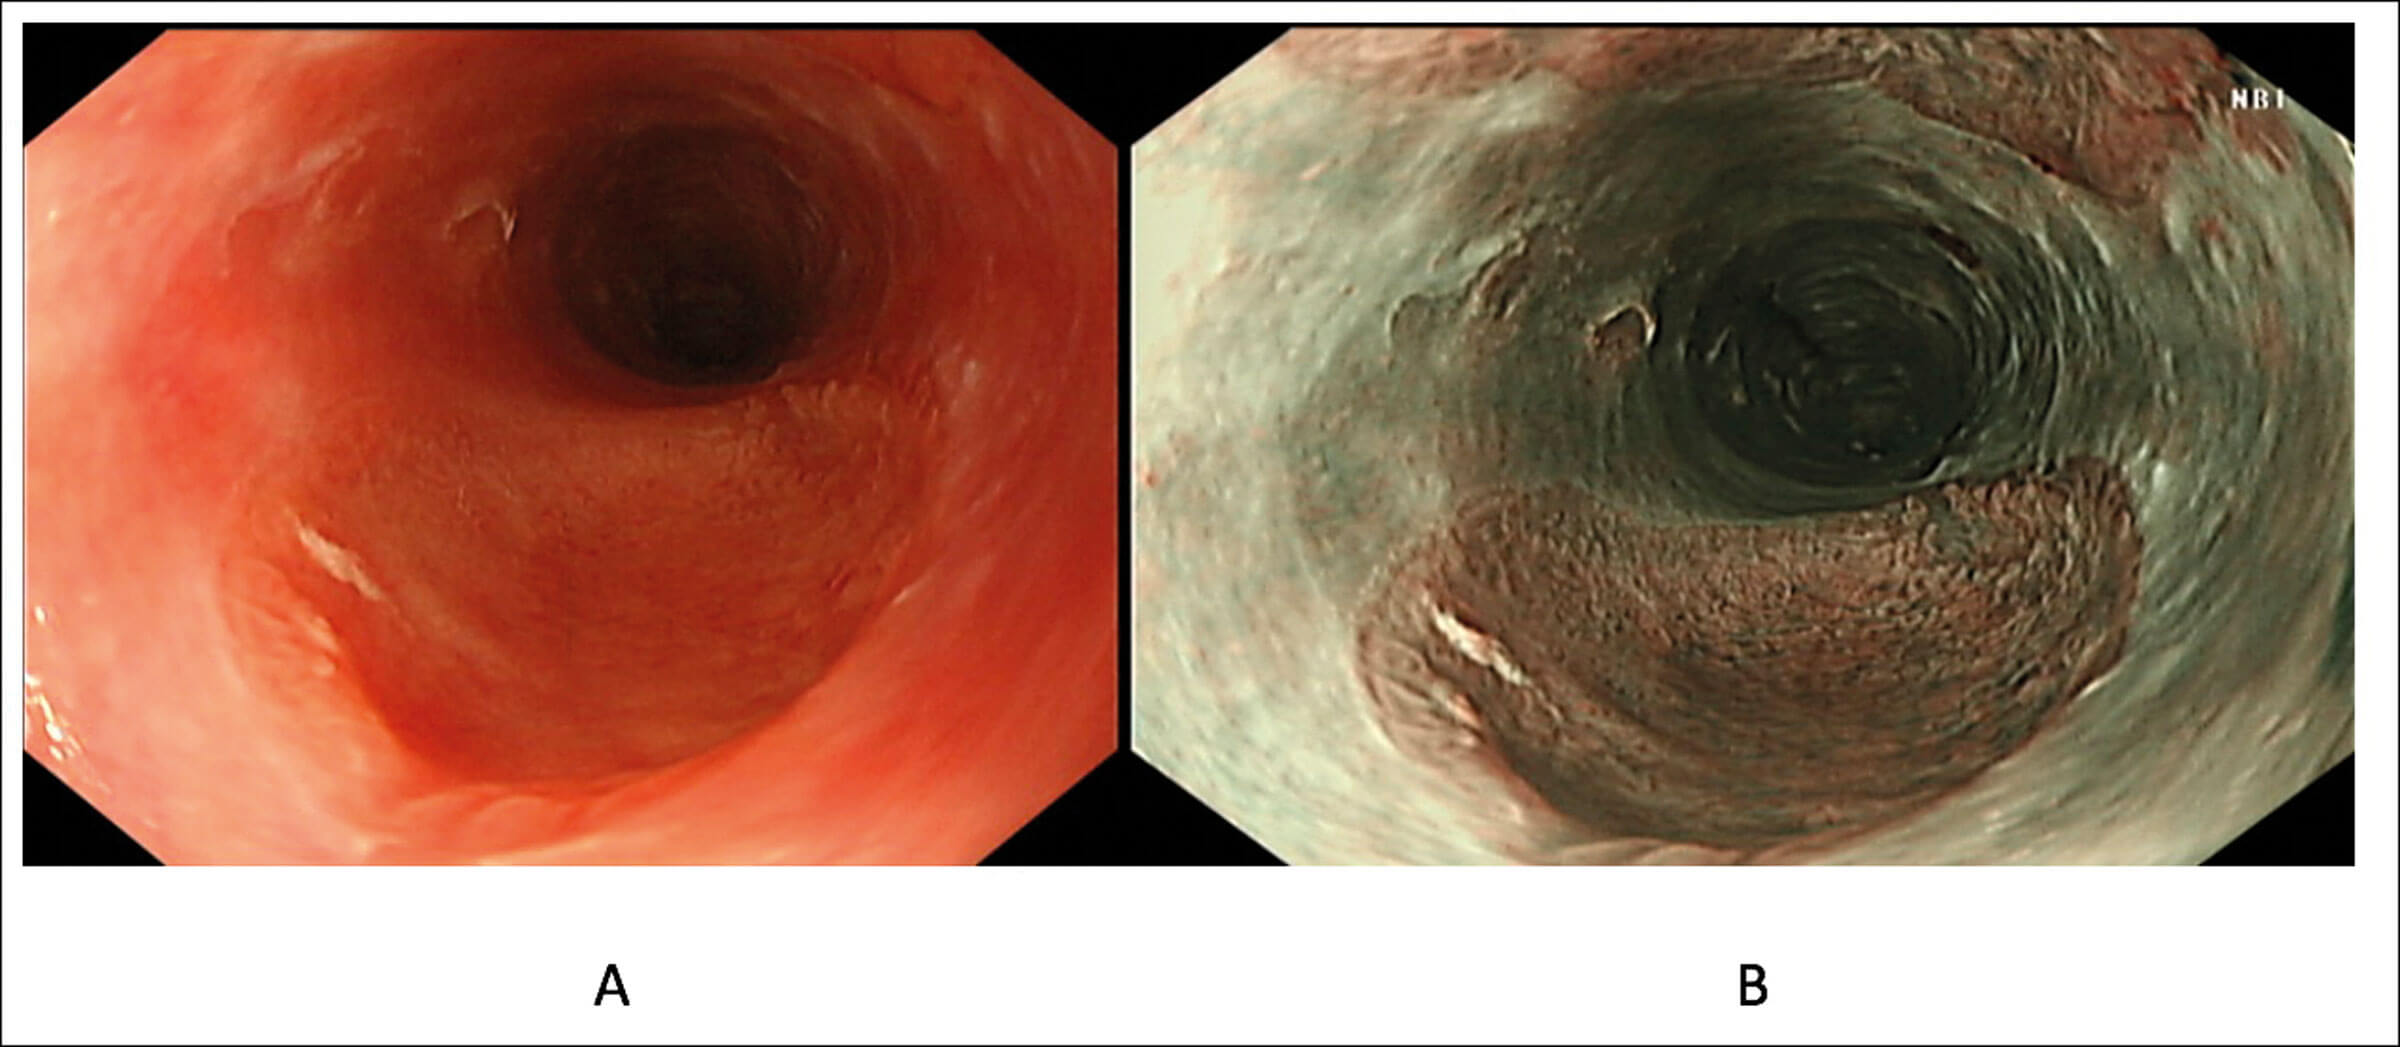

Figure 1. An inlet patch in the proximal oesophagus assessed in white light (A) and narrow band imaging (B).

An upper GI endoscopy is the gold standard for diagnosis of a GIP. It is usually identified 15-21cm from the mouth. It has the appearances of a salmon coloured and round/ovoid patch with clearly defined borders (Figure 1). It is best identified during slow withdrawal of the endoscope in the upper oesophagus with repeated short insufflations in combination with narrow-band imaging [2].